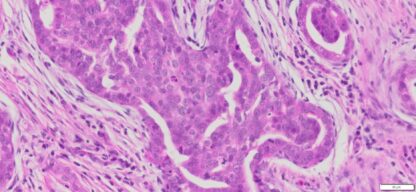

Description

| Tissue | Pathology Diagnosis | Gender/ Age (year) | %Tumor Area | Tumor Grade | TMN/Stage | IHC data |

| Omentum | Human omental high grade serous Carcinoma | Female/67 | 40% | III | NA | MOC-31(+),BER-EP4(+),P53(+), P16(+) |